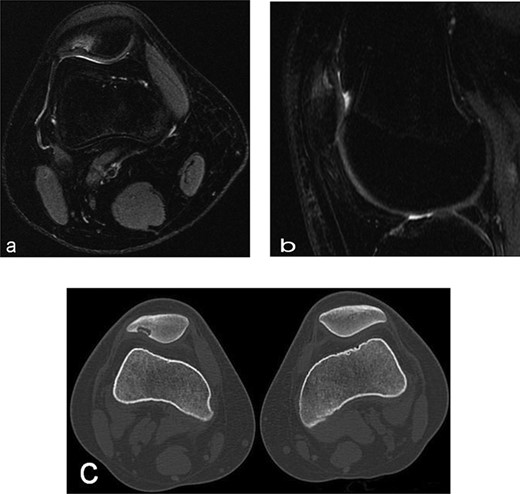

A 14-year-old female dancer presented with increasing right knee pain and functional disability without any trauma. Her pain was retropatellar pain that often radiated medially or laterally from the patella, exacerbated by climbing stairs, running and squatting. She was unable to perform any sports activities. Examination revealed peripatellar tenderness and crepitus, full range of motion and the knee was stable. Radiological examination included both MRI and computed tomography of the knee were performed at the beginning. MRI showed osteochondritis dissecans at the area at the superolateral facet of the patella in the deep subchondral area as shown in Fig. 1. This was appropriately treated conservatively with 6 months of reduced load and protected weight bearing without relief of symptoms. She quit sport activity for 2 years and then another MRI was performed Fig. 2. After 2 years we opted for adipose-derived mesenchymal stromal cells (AD-MSCs) intra-articular therapy according to the procedure described by Tremolada et al. [9]. The patient’s parents were given written information regarding the use of AD-MSCs therapy, including relative risks of this therapy and also relevant treatment alternatives that could otherwise be explored. Postoperative radiological evaluation was performed at 6 months and 12 months after AD-MSCs procedure as shown in Figs. 3 and 4. Postoperative clinical evaluation was performed using IDKC, Lysholm and Tegner scores (Table 1). After surgery, patients began a McConnell program of lateral retinacular stretching, patellar taping and vastus medialis obliquus muscle exercises. The patient was encouraged to swim and cycle to reduce impact loading. Using AD-MSC, she reported a complete relief of pain after 1 year from the procedure. Routine MRI follow-up 2 years later showed evidence of appreciable improvement in cartilage volume and osteochondral architecture at the site of injury. Early MRI T2 mapping at 6 months indicated that the area of cartilage regeneration exhibited high water content suggestive of immature cartilage or fibrocartilage morphology. Later T2 mapping at 18 months after the procedure, indicated progressive maturation of cartilage from deep to superficial layers with more hyaline like cartilage morphology. Limitations of the study are lack of arthroscopic intra-articular visualization and classification of the patella lesion.

Radiographs of the patient’s knee at 14 years old (a) Axial T2-weighted MRI sequences (b) sagital T2-weighted MRI sequences showed abnormality area at the superolateral facet of the patella in the deep subchondral area, this area of altered signal, hypointense in T1 and hyperintense in T2 with a shaded surrounding edema, was oval in morphology and had a craniocaudal extension of about 12 mm and transversal about 10 mm, the lesion interrupted the corresponding patellar articular cartilage which appears swollen in this position (c) axial computed tomography scan showed loss bone at that same point of patella in the right knee.